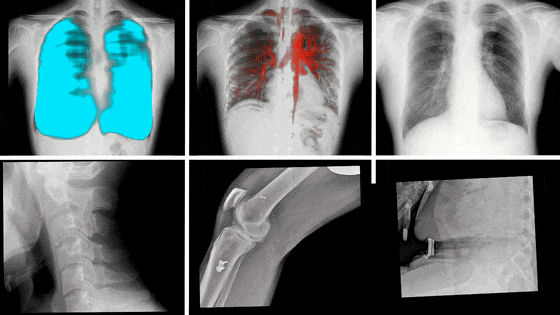

動態DR影像